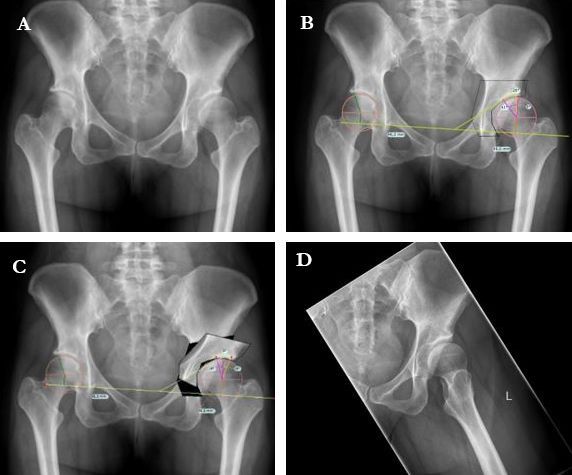

Technique L’ostéotomie périacétabulaire (OPA) mini-invasive pour le traitement de la dysplasie de la hanche chez l’adulte , G.I. Wassilew Service d’orthopédie, Universitaetsmedizin Greifswald, Ferdinand-Sauerbruchstraße, 17475 Greifswald, Allemagne , Viktor Janz Greifswald University Hospital, Fleischmannstraße 6, 17489 Greifswald, Germany 🖂 ortho@uni-greifswald.de , Jannis Löchel Greifswald University Hospital, Fleischmannstraße 6, 17489 Greifswald, Allemagne 🖂 ortho@uni-greifswald.de , André Hofer Greifswald University Hospital, Fleischmannstraße 6, 17489 Greifswald, Allemagne 🖂 ortho@uni-greifswald.de , Richard Kasch Greifswald University Hospital, Fleischmannstraße 6, 17489 Greifswald, Germany 🖂 ortho@uni-greifswald.de N°297 - Octobre 2020 ● 15 min de lecture